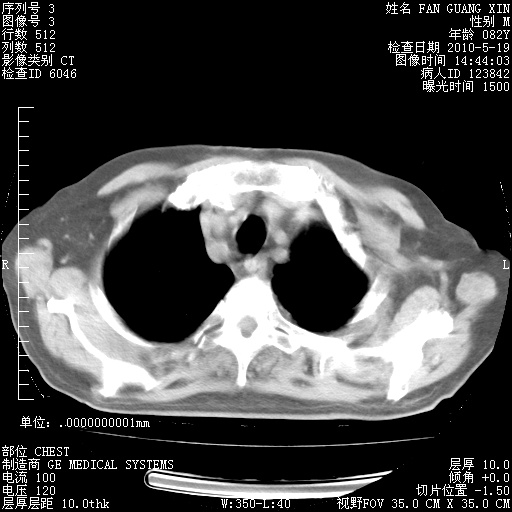

复查肺部CT,明显好转。为什么发热呢?

治疗3周后的肺部CT

治疗3周后的肺部CT纵隔窗